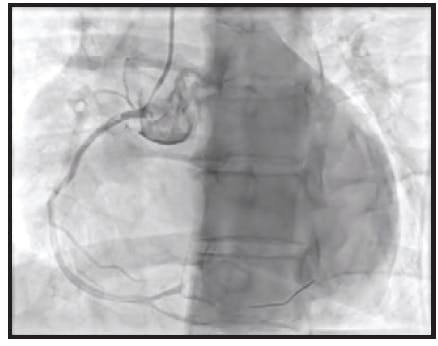

A 65-year-old man presented emergently with an inferior wall MI. The initial angiogram confirmed a distal occlusion of the RCA with TIMI 0 flow and extensive clot burden (Figure 1).

Initial angiography revealed an occlusion of the distal RCA. Mechanical coronary aspiration was performed frontline with CAT RX and Penumbra ENGINE to remove the high thrombus burden. After one pass with CAT RX, the high thrombus burden was removed, resulting in TIMI 3 flow.

With reperfusion to the distal vasculature and clear visualization of the underlying stenosis, a 3.5-mm stent was placed. After IVUS, the stent was dilated to 3.75 mm. Final angiography was performed, showing complete resolution of the underlying lesion (Figure 2).